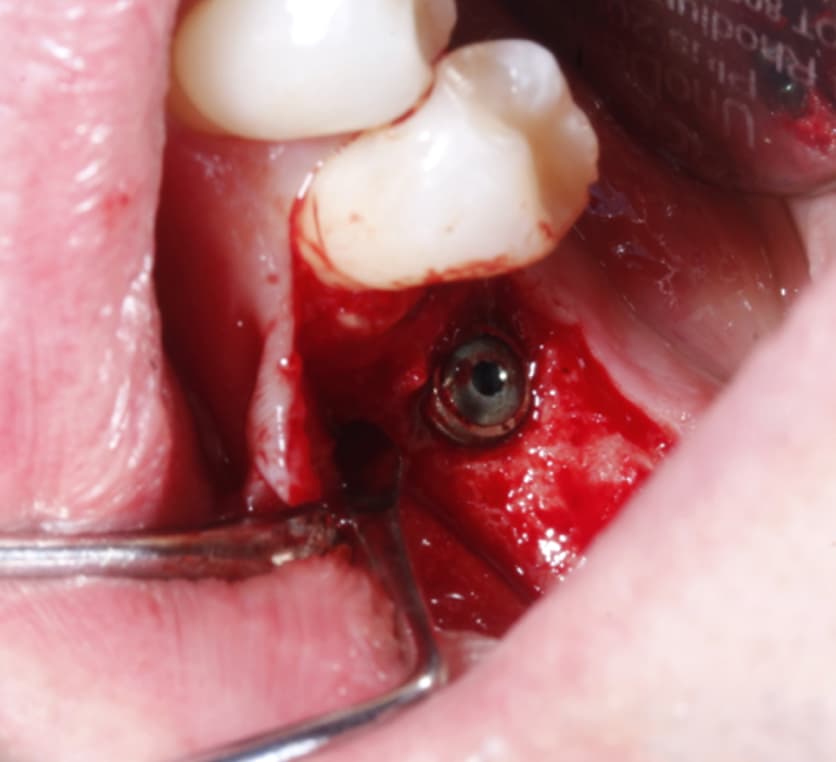

( after 3 months, implant was uncovered but the buccal cervical bone is missing , there is no denture use at all and the buccal wall just disappeared. there was no bone graft or membrane used when the implant was placed)

at the end, Ethoss, beta-TCP was grafted and moulded around the implant to close again.

could anyone explain how this buccal wall disappear after implant placement?